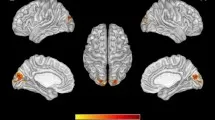

Корреляция показателей ДТВ и мотивации

Были проведены двумерные анализы балла CMS и показателей ДТВ в априорных регионах. Статистически значимые корреляции между CMS и fractional anisotropy (FA — фракционная анизотропия, мера направленной зависимости диффузии воды, отражающая микроструктурную целостность белого вещества), mean diffusivity (MD — средняя диффузия, средняя величина диффузии воды во всех направлениях) и radial diffusivity (RD — радиальная диффузия, диффузия воды перпендикулярно основному направлению волокон) показаны в соответствующей таблице. Отрицательные корреляции наблюдались между CMS и FA в передней ножке внутренней капсулы с обеих сторон и superior corona radiata (справа), и положительные корреляции с MD в поясной извилине (справа) и RD в поясной извилине (с обеих сторон).

Нейровизуализационные аспекты мотивации

Используя ДТВ, мы identified взаимосвязь между баллом мотивации и микроструктурой белого вещества, similar to исследованиям апатии и ВИЧ у взрослых. В частности, показатели ДТВ в передней ножке внутренней капсулы, superior corona radiata и поясной извилине коррелировали с баллом CMS, что suggests целостность белого вещества в этих регионах связана с мотивацией.

Направление изменений и интерпретация

Более высокая мотивация была связана с lower FA, мерой целостности белого вещества, в то время как lower мотивация была связана с higher MD и RD в specific фронтостриатальных регионах. Направление эффекта similar to корреляциям между показателями ДТВ и мотивацией, о которых previously сообщалось у подростков, однако оно отличается от некоторых предыдущих исследований у взрослых, живущих с ВИЧ.